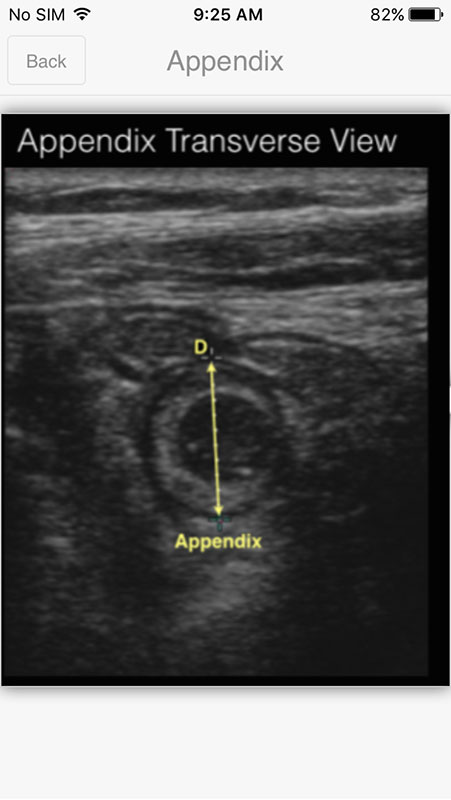

Selecting the subcategory opens a screen with an ultrasound image of the specific organ. Images are labeled, pointing out specific structures in normal anatomy. Some of the subcategories also contain normal expected values for particular organs. There are also abnormalities in some of the categories tho, but they do not contain ultrasound images, only textual description of pathology values (for example in Ovaries category where Ovarian torsion is explained besides normal image).

For those categories that have an image, there's only one image that features just one view, which, in my opinion, isn't sufficient to show normal ultrasound anatomy. There should be multiple images from different angles, and perhaps even comparisons to an illustrated images depicting the organ.

To see the image in more detail, you just need to tap on it, which expands the image (zooms in). However, this part isn't implemented so well. The image expands outside the screen and there's no option to fit it inside. The horizontal rotation doesn't work, so users are stuck with a vertical view, which isn't mobile friendly.

Also, the app creators claim that images are high quality, but in reality, they're not. They stay the same resolution when you expand them, only looking a bit grainier. I expected this part to be much better in the app that focuses on ultrasound imaging.